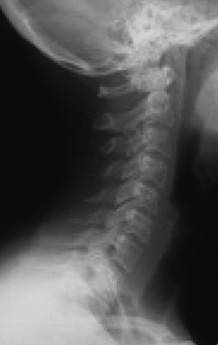

Причем, опять же, рост этого горбика она объясняет исключительно «солями» – остеохондрозом – и не связывает с изменившейся статикой своего позвоночника. В норме позвоночник, как известно, не должен быть прямым, как палка, а иметь физиологические изгибы. В частности, шейный отдел, состоящий из 7 позвонков, в норме должен быть чуть прогнутым внутрь (рис. 13).

Рис. 13. Нормальная статика шейного отдела